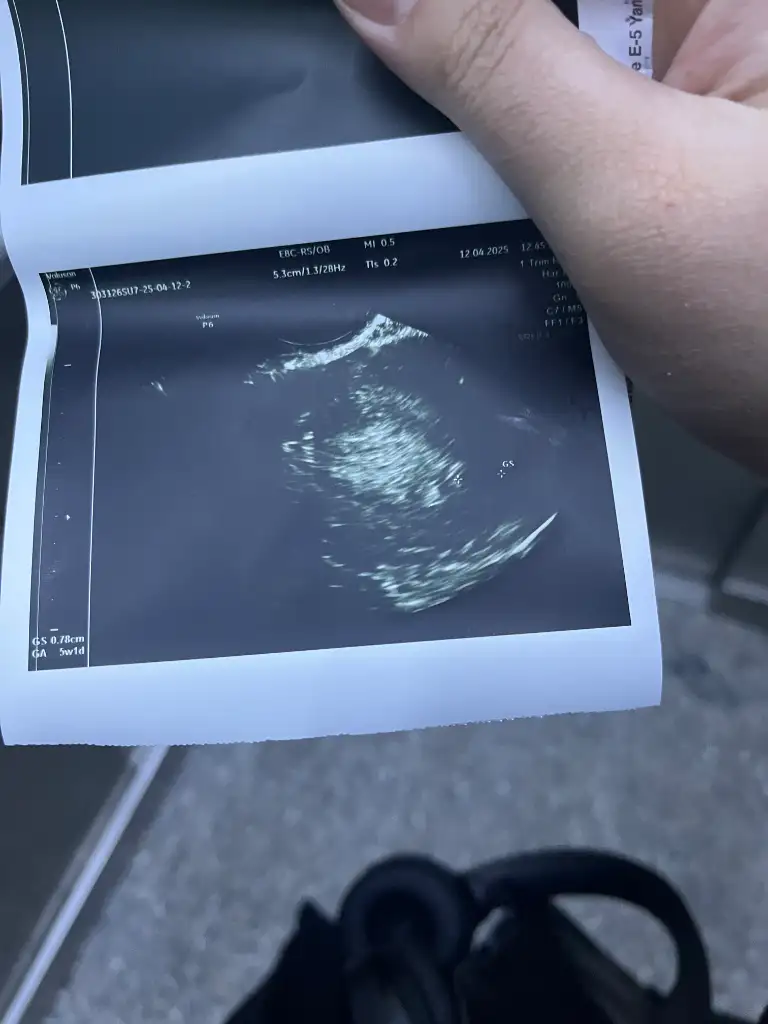

Kese göründü betaya baktı 2135 olmuş pazartesi tekrar gel dedi dış gebelik değilmiş şu anda normal dediNe yaptın gittin mi doktara ben de gittim kese gördü doktor ama içindeki emriyo gelişmez dedi değerlerin düşüşe geçti dedi kürtaj olmamı istedi (bu gittiğim başka bir doktordu nöbetçi)

Arkadaşlar aranızda yeniyim gecen hafta Perşembe kadın doguma gıttım karından utroson ile bakıldı bebek gozuktu 5 haftalık dedi beta aldı 91.33 cıktı 2 cıye bugun verdım 119.50 çıktı beta artıs sızce nasıl artıs normalmı27 mart beta hcg 5

5 haftalık gebelik için değeriniz düşük. Karında bu hcg değeri ile görmesi imkansız gibi birşey. Bide tam bir hafta falan geçti doğru anladım değil mi hcg değeri böyleArkadaşlar aranızda yeniyim gecen hafta Perşembe kadın doguma gıttım karından utroson ile bakıldı bebek gozuktu 5 haftalık dedi beta aldı 91.33 cıktı 2 cıye bugun verdım 119.50 çıktı beta artıs sızce nasıl artıs normalmı